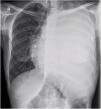

Initial laboratory tests showed normocytic anemia (Hb 11.3g/dL), leukocytes 3820/μL (87% neutrophils), and platelets 226,000/μL, with normal renal and hepatic function. Chest X-ray at admission demonstrated complete opacification of the left hemithorax with contralateral mediastinal shift (Fig. 1).